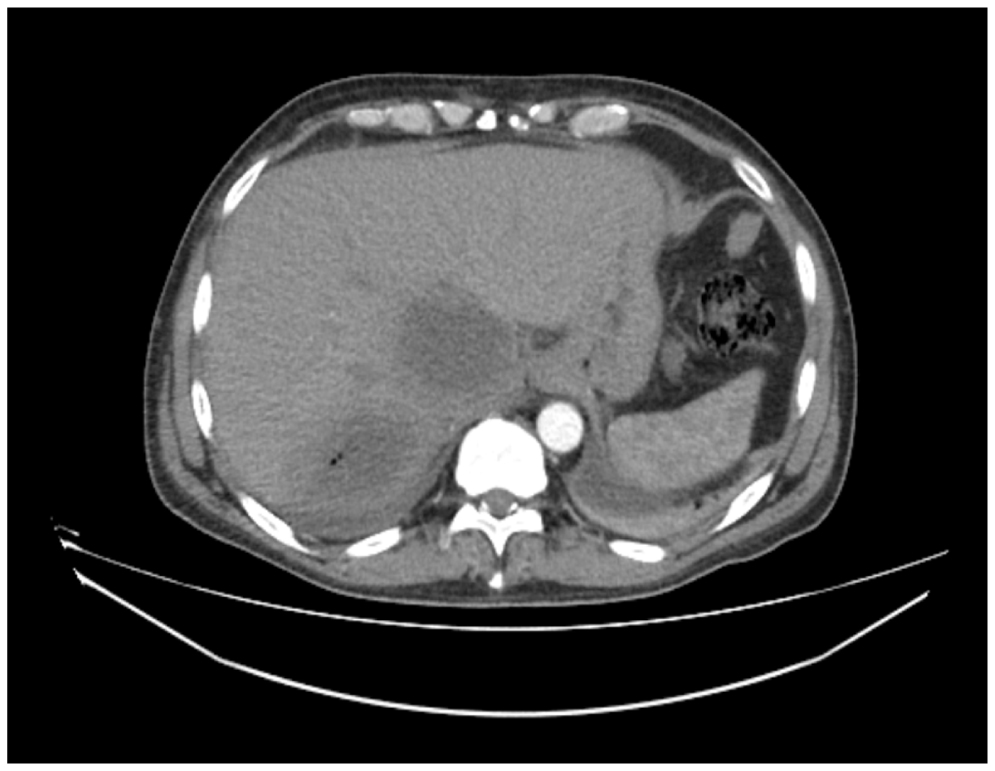

On the 19th day of illness, a non-enhanced computed tomography (CT) of the chest and abdomen was conducted because the patient’s condition had not improved despite the administration of various therapeutic agents, including antibacterials (levofloxacin, vancomycin, and meropenem) and human immunoglobulins. Bilateral ground-glass opacity and right-sided partial atelectases in the lower and median lobes were visualized on CT scans. The 50×72×70-mm abscesses were detected in the hepatic segment 6 (S6). A similar 61×47×65-mm lesion was found in the S5 segment. The fluid was visualized in the pelvis (up to 47 mm) and in the lesser sac (179×69 mm; Figures 1 and 2).

Fig. 1. Computed tomography of the abdominal cavity.